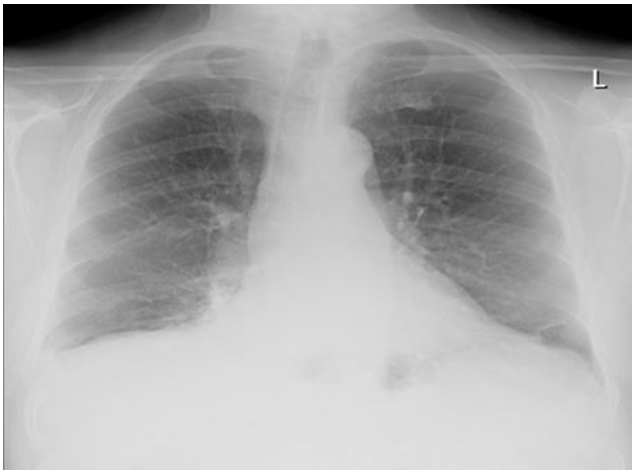

His chest x-ray (see figure 1) showed right-sided consolidation in keeping with community-acquired pneumonia. Blood showed raised inflammatory markers (table 1). He received IV antibiotics and steroids for community-acquired pneumonia. CT angiogram/ CAP Note is made of metastatic bony changes already recorded and described on a bone scan from 05/10/2022. I suspect further progression of the metastatic bony deposits now. Most of the thoracic vertebra are now affected by metastatic bony disease. There are also metastatic deposits in the sternum and the ribs - already recorded on the previous bone scan. Note is made of moderate rolling hernia of the stomach. Incidental note is made of 4.4 mm across opaque stone in the calyx of the upper moiety of the left kidney

Figure 1: Chest x ray showing dense right sided consolidation in keeping with clinical examination and representing community acquired pneumonia